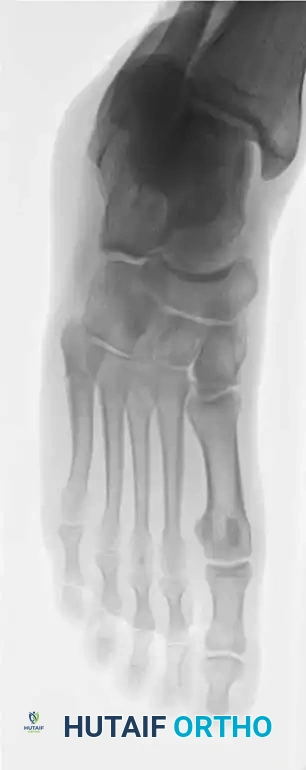

Fig. 86-44 A-C, Type IIIB (DeLee) fi fth metatarsal fracture.

Fig. 86-44 A-C. Preoperative radiographs of a Type IIIB (DeLee) fifth metatarsal fracture demonstrating significant intra-articular displacement requiring surgical reduction.